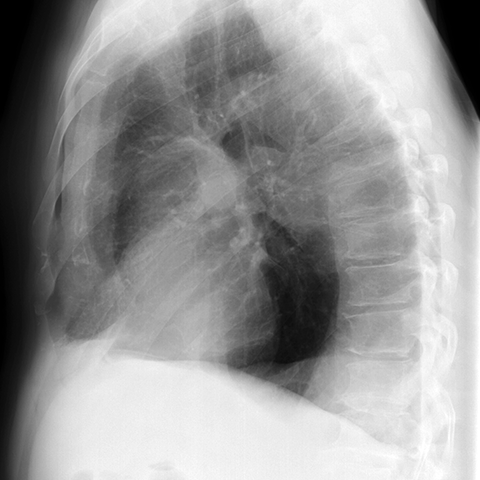

LLL Atelectasis [2 of 4]